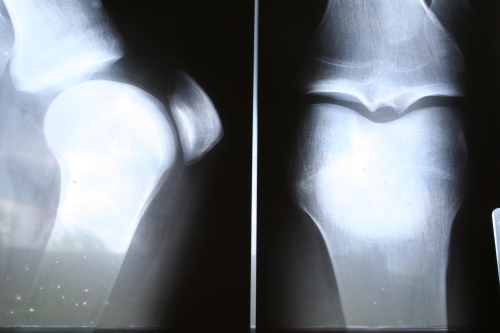

Se malattie cardiache e diabete sono già di per se motivi sufficienti per iniziare a pensare di dimagrire, ecco un altro motivo importante per farlo: essere in sovrappeso o obesi può causare un rapido deterioramento della cartilagine del ginocchio, e ciò può condurre facilmente ad un disturbo comune nelle persone sopra i 50 – 60 anni, l’osteoartrite.

La ricerca è stata impostata sullo studio di 336 pazienti già coinvolti in un altro studio sulla osteoartrite. Tutti erano in sovrappeso, ed a rischio di osteoartrite, sebbene per nessuno di loro ci fossero ancora i segni di deterioramento della cartilagine del ginocchio.

Dopo 30 mesi di ricerca, sul 20,2% dei pazienti è stato riscontrata una lenta degenerazione della cartilagine, mentre per il 5,8% la degenerazione è stata decisamente più rapida.

Sovrappeso ed obesità sono stati dunque associati ad una rapida degenerazione dei tessuti cartilaginei, ed i ricercatori hanno verificato che, per ogni punto in più di aumento dell’indice di massa corporea, la possibilità che la degenerazione progredisse rapida è stata calcolata intorno all’11%.

L’associazione tra obesità e rapida degenerazione della cartilagine è rimasta inalterata nelle sue proporzioni anche quando i ricercatori hanno provato a differenziare i pazienti in base ad età, sesso e origine etnica.